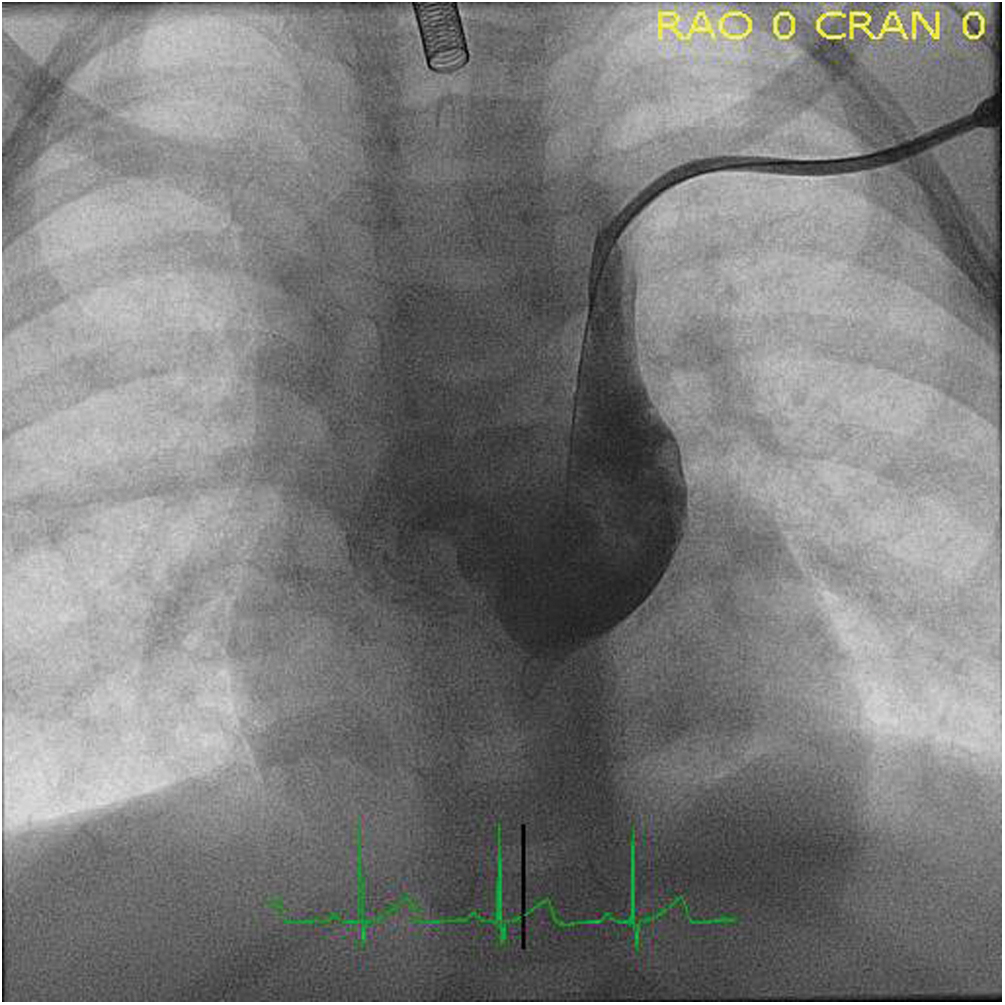

The patient subsequently underwent cardiac catheterization. Angiography confirmed earlier imaging findings (Fig. 3), and the PLSVC was successfully occluded with a 10 mm Amplatzer Vascular Plug II distal to the bridging vein (Fig. 4). Following the procedure, the patient’s positional hypoxemic episodes resolved. The patient has weaned off mechanical ventilation during the day, and is currently weaning from respiratory support during sleep.

Figure 3: Angiography with contrast injection in the PLSVC demonstrating drainage into the left atrium